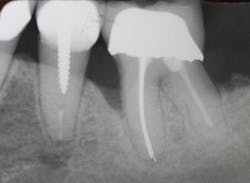

A patient had four quadrants of scaling and root planing in the office of her general dentist. Subsequently, three maxillary anterior implants were placed. The patient was scheduled every six months for periodontal maintenance visits. Radiographs taken prior to the scaling and root planing (figure 4) revealed moderate periodontitis with slight vertical bone loss involving the mandibular left first molar. A deep vertical osseous defect on the distal of the second molar was present.